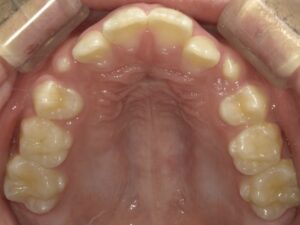

実際に上記の治療をされた患者さんです。

治療前はこのように歯並びのアーチが狭く、

これから生え代わる大人の歯がきれいにならばないと予想しました。

治療を始めた後の写真です。

大人の歯に生え代わりましたが、きれいな歯ならびのアーチになってきています。

スペースは十分に確保できてきたので、